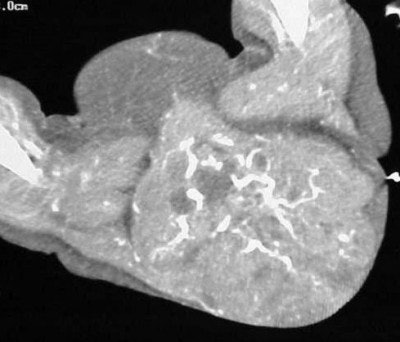

In figure TC 3 we can see a large soft-tissue mass measuring approximately 9 cm wide by 6 cm in AP diameter, and 14 cm in height. It contains both fluid and semi-solid components of soft tissue as well as assorted calcifications. The mass appears to terminate (Figure TC 4) just above the level of the uterus (arrow).

The images (Figures TC 5 and TC 6) show, respectively, a sagittal and coronal MPR of the axial images, demonstrating the size and volume of the structure.